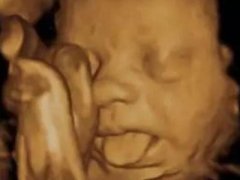

• 怀孕后的准妈妈们记住你不能吃什么

怀孕后的准妈妈们记住你不能吃什么